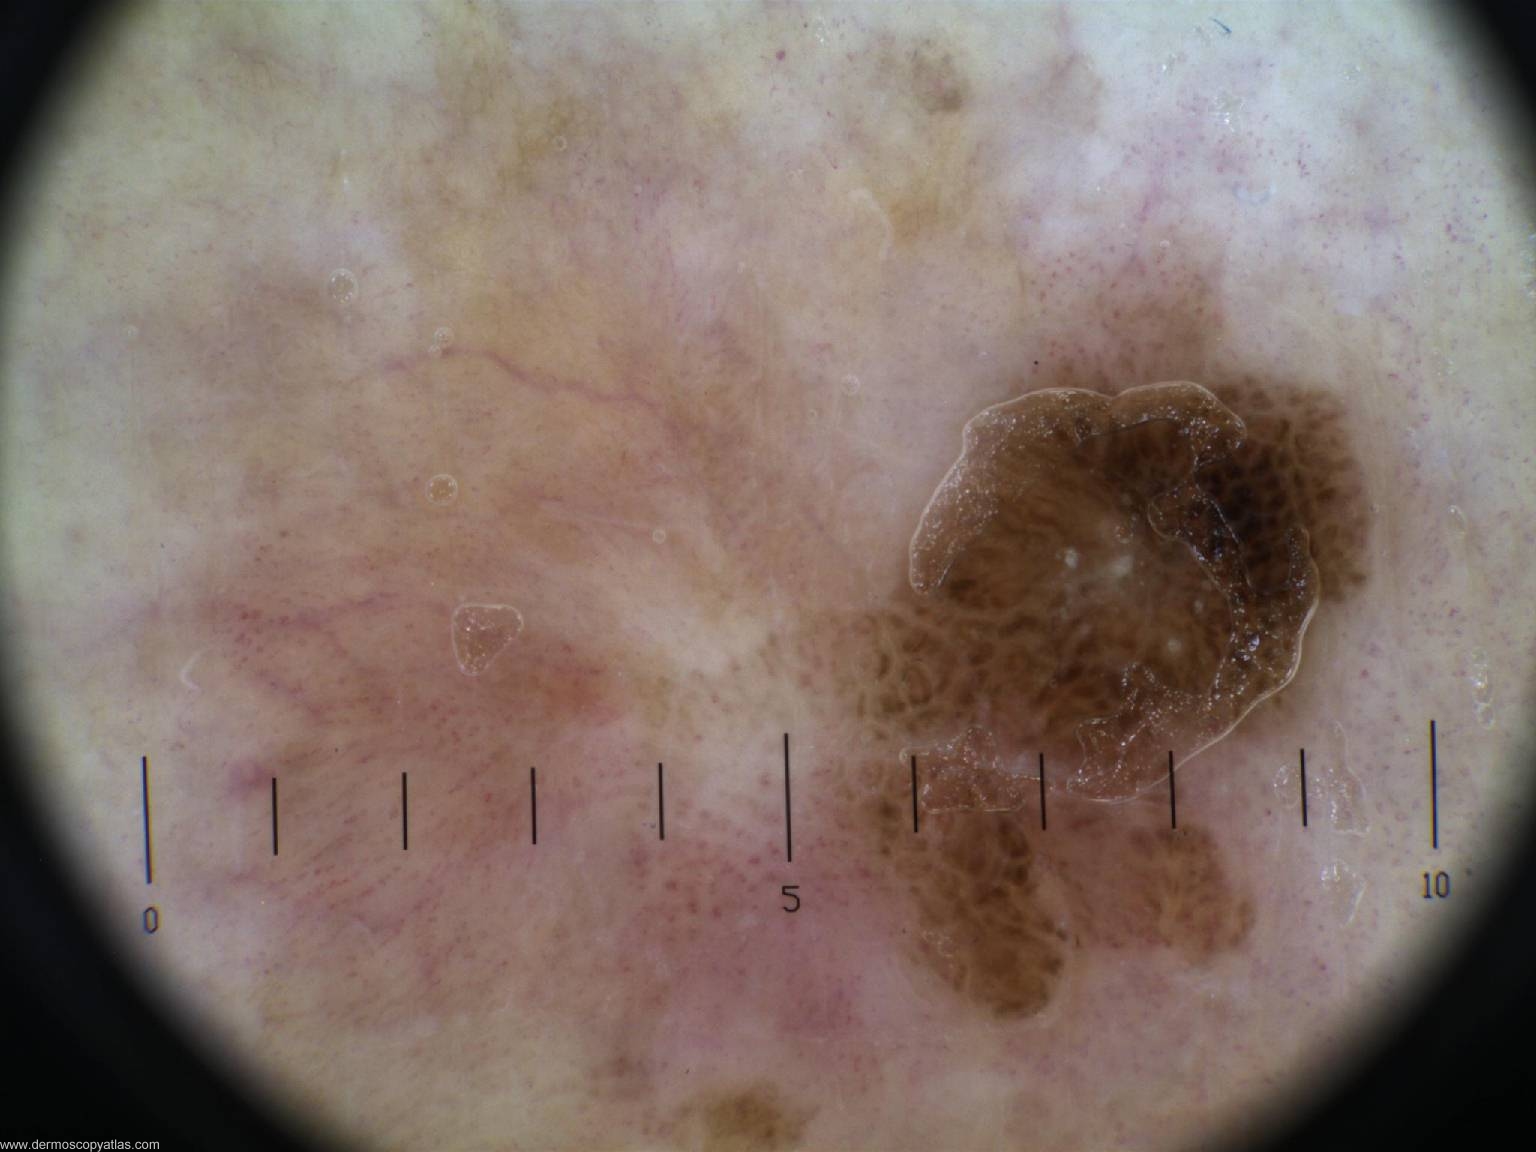

This was the December 2007 Dirty Dozen composed by Dr Tim Hackett. Case 1 72 year old female with a lesion noted on the lower leg. Present for many years according to patient.

Question: What is the diagnosis? Consider Melanoma, Seborrhoeic keratosis, Pigmented IEC, Pigmented BCC, Dysplastic nevus.